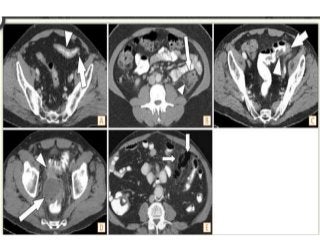

Axial CT image demonstrates left

colonic wall thickening,

pericolonic fat stranding, fascial

thickening (arrowheads) and an

inflamed diverticulum (arrow).

Axial CT image shows an ileal

diverticulum (arrow) with

surrounding inflammation

(arrowheads). Thin arrow =

normal appendix

Axial CT image shows free

fluid (long arrow), jejunal

diverticula,thickened walls of

duodenal and jejunal loops

and mesenteric fat stranding

(both short arrows)

Investigations - CT

Air-filled diverticula

Mesenteric stranding